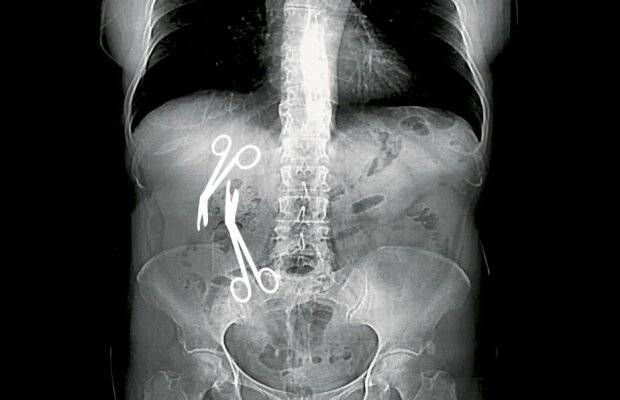

INVESTIGAȚIE EXCLUSIVĂ/ Chirurgul Gheorghe Ștefan lovește din nou! După foarfeci, a uitat și "un ghem" de ațe într-un alt pacient!

INVESTIGAȚIE Libertatea / Directorul medical al Spitalului Militar din Constanța a uitat două foarfeci de 16 cm în burta unei paciente de 61 de ani!